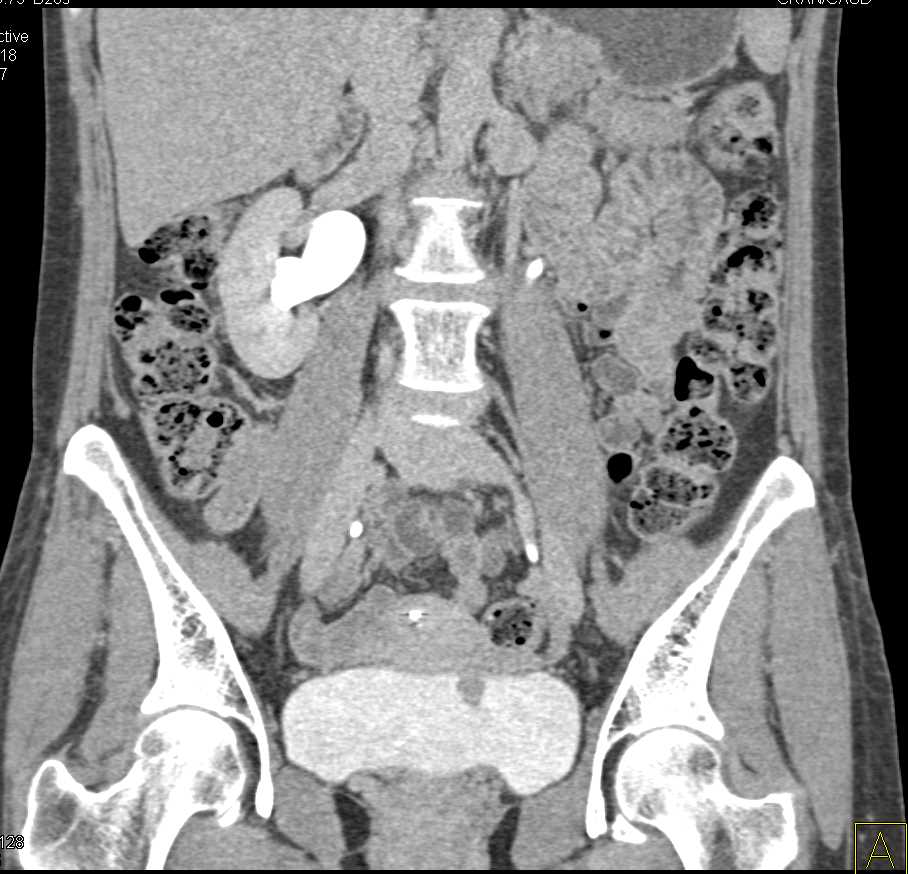

Bladder Cancer with Active Bleed